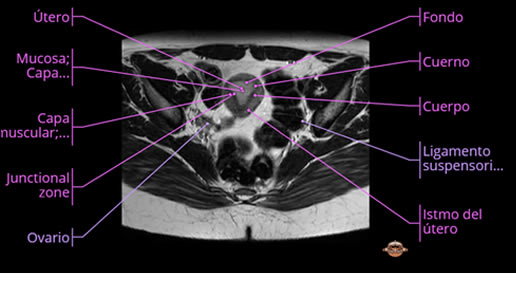

Se realizan adquisiciones en diferentes planos, con secuencias Spin echo y GRE, ponderadas a T1 y a T2, se utilizan pulsos de saturación de grasa y se administra medio de contraste a base de gadolinio.

El útero está en retroversión, retroflexión, y en posición central, se observa liquido en la cavidad endometrial, debido a la presencia de un Ca endometrial; en el anexo derecho se observa una masa quística que mide 3.8 x 2.2 cm de diámetro, corresponde a un quiste bilobulado, posee pared gruesa con componente solido puede tratarse de un Cistoadenocarcinoma, el cual realza con el medio de contraste de forma importante, entra dentro de una clasificación O-Rad tipo IV compatible con un Cistoadenocarcinoma